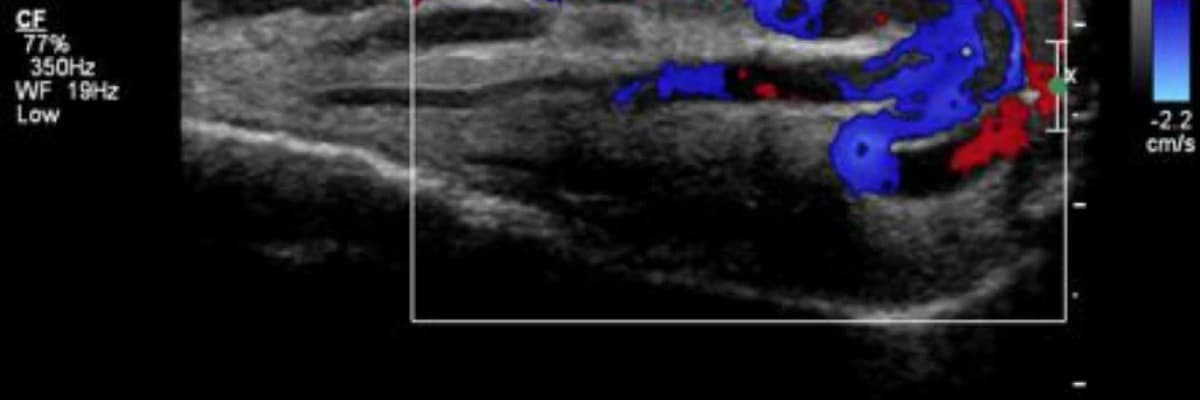

- Radyolojik Doğrulama: Fiziksel bulgular, Doppler ultrason görüntülemesi ile kesinleştirilir.

Doppler ultrason değerlendirmesinde, normalde çok daha küçük olması gereken testis toplardamarlarının aşırı genişlediği, gri zemin üzerinde büyük kırmızı ve mavi renk lekeleri şeklinde net bir şekilde görülür.